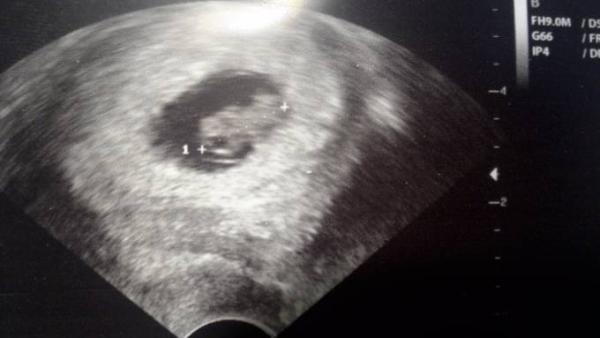

heute morgen war ich das erste mal beim Arzt. Das Herzchen pocht, alles sieht super aus. Bin von 8+2 auf 8+0 zurück datiert worden, aber ich hab eh einen unregelmäßigen Zyklus, damit hatte ich gerechnet. Mutterpass darf ich Anfang nächster Woche holen und das nächste mal in der ersten Januar Woche hin.

Ich wurde zwar von 6+6 auf 6+3 zurückgestuft, aber damit hatte ich fast gerechnet. Aber man konnte schon das Herzchen schlagen sehen

Der Krümel ist jetzt gute 4mm groß und ich habe am 19.12. den nächsten Termin, wo ich dann meinen Mutterpass und alles bekomme